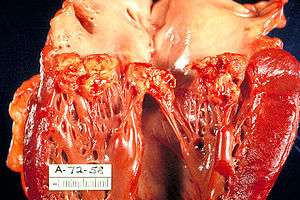

| A mitral valve vegetation caused by bacterial endocarditis. | |